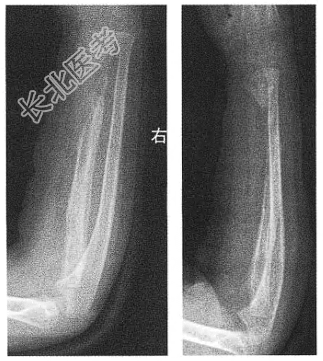

[材料题] 患者,男性,8岁。右前臂肿痛20天,发病时皮温较高,体温达39℃。实验室检查:WBC12.05×109/L,中性粒细胞79%。右尺桡骨正侧位DR片如图。

单项选择题1.最可能的诊断是( )。

单项选择题2.本例主要需与何种疾病加以鉴别( )。

单项选择题3.诊断困难时,常可采用什么方法进行鉴别( )。